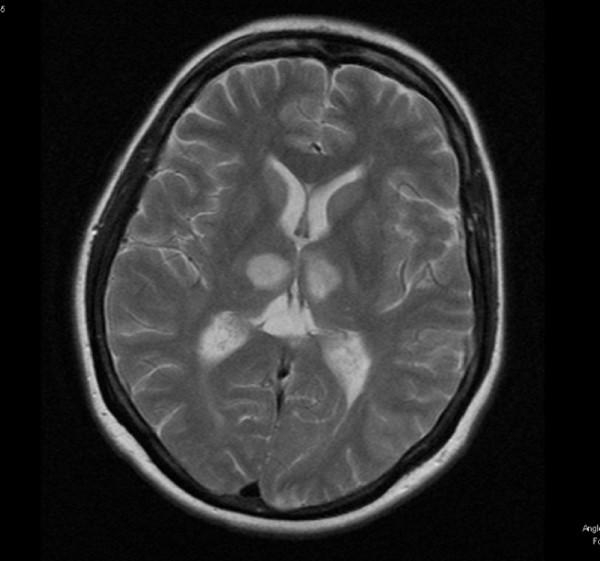

Unexplained rapid onset of confusion with amnesia and minimal neurological deficits can be a manifestation of various systemic causes of which stroke, either ischemic or hemorrhagic, is one. Thorough and systematic evaluation of these patients can be highly rewarding in terms of optimizing patient outcome. We report the case of a 45-year-old woman whose initial presentation was with acute onset of confusion, memory loss with personality change and headaches. A differential diagnosis of systemic illness and cerebral pathology was entertained. She was empirically treated for neurological infection. Brain imaging revealed bilateral thalamic and cerebellar infarction. Further evaluation with an aim to define the etiology, revealed the diagnosis of Patent Foramen Ovale with paradoxical embolism. The differential diagnosis of unexplained rapid onset of confusion, amnesia with minimal motor neurological deficits and relevant appropriate investigations are discussed in this case report.

原因不明的快速出现的意识模糊伴失忆且神经功能缺损轻微,可能是多种全身性病因的表现,其中缺血性或出血性中风是病因之一。对这些患者进行全面系统的评估,在优化患者预后方面可能会有很大收获。我们报告一例45岁女性,其最初表现为急性意识模糊、记忆力丧失伴人格改变及头痛。考虑了全身性疾病和脑部病变的鉴别诊断。她接受了针对神经感染的经验性治疗。脑部影像学检查显示双侧丘脑和小脑梗死。进一步评估以明确病因,诊断为卵圆孔未闭伴反常栓塞。本病例报告讨论了原因不明的快速出现的意识模糊、失忆伴轻微运动神经功能缺损的鉴别诊断及相关的适当检查。